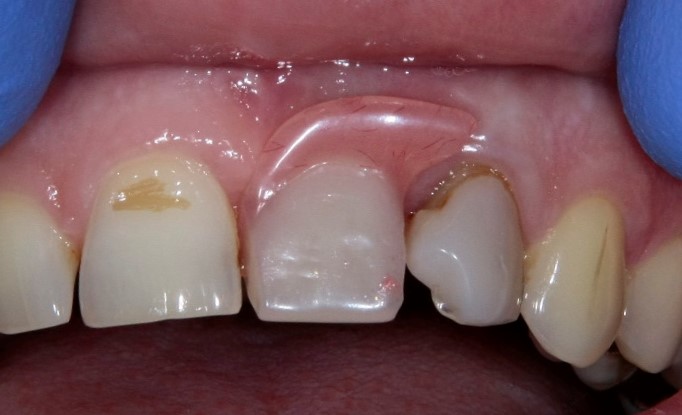

В таких случаях пациенту нередко предлагается какая-то съемная протетическая конструкция (в народе называемая «бабочкой» или «жучком»), задача которой — замаскировать отсутствие зуба до его восстановления с помощью импланта:

И, я должен заметить, что с маскировкой такой простейший протез отлично справляется: